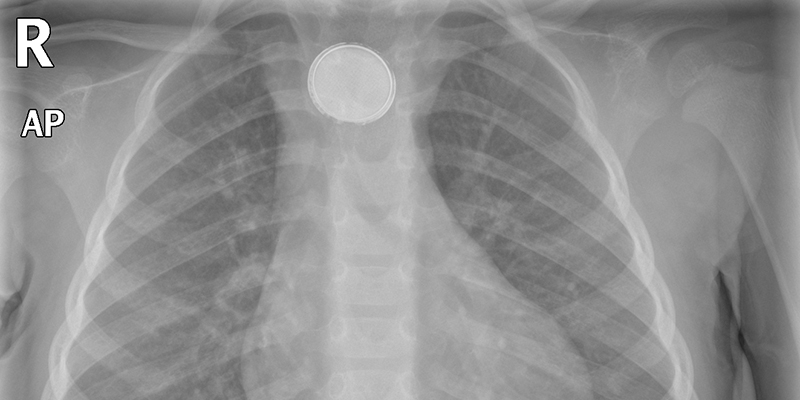

De meeste kinderen (n = 304; 81%) ondergingen binnen 24 uur na inname röntgendiagnostiek (mediaan 8,5 uur; 0,5 uur tot 12 dagen). De belangrijkste redenen waarom er geen röntgenfoto werd gemaakt waren het ontbreken van toestemming van ouders/verzorgers of een afwijkend behandelbeleid door artsen.

Bij 209 kinderen (56%) werd ten minste één batterij aangetroffen (op basis van een röntgenfoto of endoscopie, of in de ontlasting); bij 206 kinderen (99%) was dit een knoopcelbatterij en bij drie kinderen (1%) een staafbatterij.

Na inname van kleine knoopcelbatterijen (< 15 mm) passeerde 98% (158 van de 162 kleine knoopcelbatterijen) spontaan het maag-darmkanaal; follow-uponderzoek liet geen complicaties zien. Endoscopie werd uitgevoerd bij 26 kinderen (7%), bij wie in totaal 28 knoopcelbatterijen werden verwijderd. De verwijderde batterijen bevonden zich in de slokdarm/keel (25%, n = 7) of in de maag (75%, n = 21). De mediane tijd tussen inname en endoscopie was 72 uur (minimaal 2 uur, maximaal 13 dagen) bij kinderen met batterijen in de maag en 8 uur (minimaal 4,5, maximaal 24 uur) bij kinderen met batterijen in de slokdarm/keel. Late verwijdering was voornamelijk het gevolg van het afwachtend beleid van artsen (wachten tot spontane passage had plaatsgevonden), maar ook doordat een aantal ouders kort na de blootstelling geen arts raadpleegde. Negen van de 26 kinderen (35%) hadden lokale slijmvliesbeschadiging: erosie/ulceratie van het slokdarmslijmvlies (6 maal), proximale oesofagitis (2 maal) of irritatie/laesies van het maagslijmvlies (3 maal). Voor verwijdering vertoonden 6 van de 9 patiënten met laesies symptomen (meestal braken of misselijkheid); de overige 3 waren asymptomatisch. In totaal werden bij 18% van de patiënten symptomen gemeld (n = 69). Bij 14 patiënten was sprake van een donkere stoelgang en/of melena (4%). Alle kinderen met lokaal letsel herstelden goed en late complicaties werden niet gemeld.